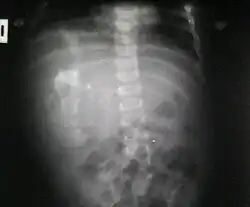

Fetus in fetu

Fetus in fetu (or foetus in foetu) is a rare developmental abnormality in which a mass of tissue resembling a fetus forms inside the body of its twin. An early example of the phenomenon was described in 1808 by George William Young.[1]

There are two hypotheses for the origin of a fetus in fetu. One hypothesis is that the mass begins as a normal fetus but becomes enveloped inside its twin.[2] The other hypothesis is that the mass is a highly developed teratoma. Fetus in fetu is estimated to occur in 1 in 500,000 live births.[3]